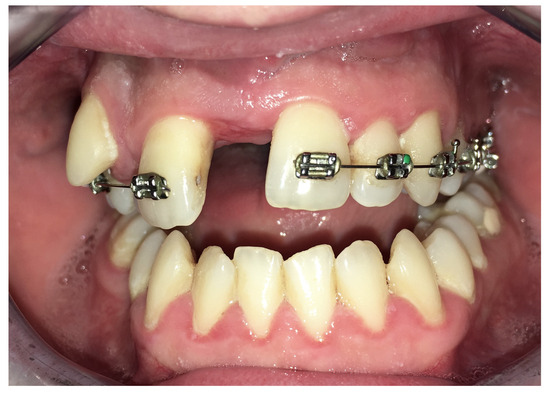

| No possibility of distraction—1 case | Maxillary incisor root resorption—2 cases |

| Perforation of the maxillary alveolar process caused by the distractor—1 case | Maxillary incisor necrosis—2 cases |

| Asymmetric distraction—5 cases | |